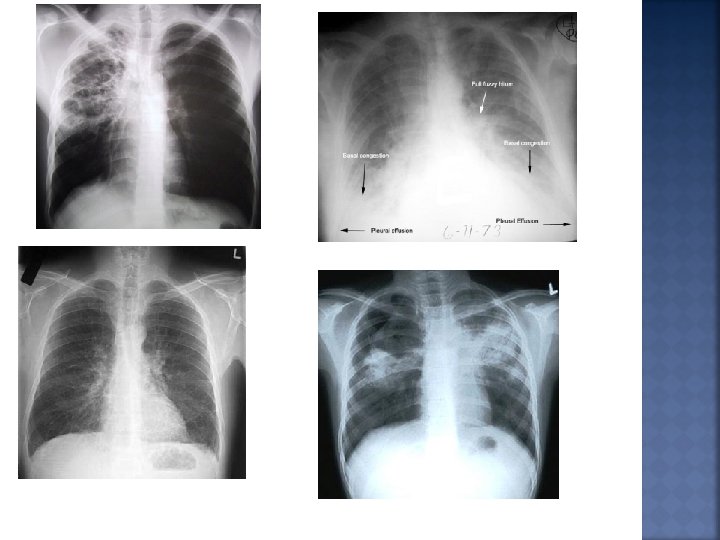

Bronchitis Inflammation of the mucous membranes of the bronchi. Causes: Associated with smoking, pollution, and bacterial or viral infections.

Pneumonia Acute inflammation of the lungs. Symptoms: high fever, chills, headache, cough, and chest pain. Causes: Bacterial, fungal, or viral infections. Treatment: Antibiotics or other antimicrobials.

Emphysema: Permanent and irreversible destruction of alveolar walls, resulting in ………. Loss of lung elasticity and gas exchange surface.

Emphysema: Symptoms: shortness of breath, difficulty breathing, cough, weakness, anxiety, confusion, heart failure and respiratory failure. Causes: Smoking, pollution, old age, and infections. Treatment: Oxygen to help breathing. No cure.

Tuberculosis A specific bacteria that infects the lungs. The formation of a Tubercle and then infection results in the loss of elasticity of the capillaries around the alveoli causing poor gas exchange.

Lung Cancerous tumors grow and destroy the lung tissue. Symptoms: bloody sputum, persistent cough, difficulty breathing, chest pain Causes: Smoking (50% of all cases) and pollution (radon, asbestos). Treatment: Surgery is most effective, but only 50% of all lung cancers are operable by time of detection. Other treatments include radiation and chemotherapy.